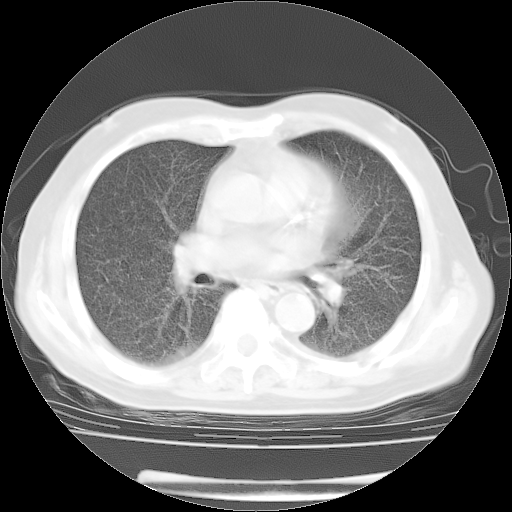

4月28日肺部CT——再次出现类似去年5月9日——透光度降低,“间质性”改变。

4月28日肺部CT——再次出现类似去年5月9日——磨玻璃样、间有“粟粒样”改变。

4月28日肺部CT